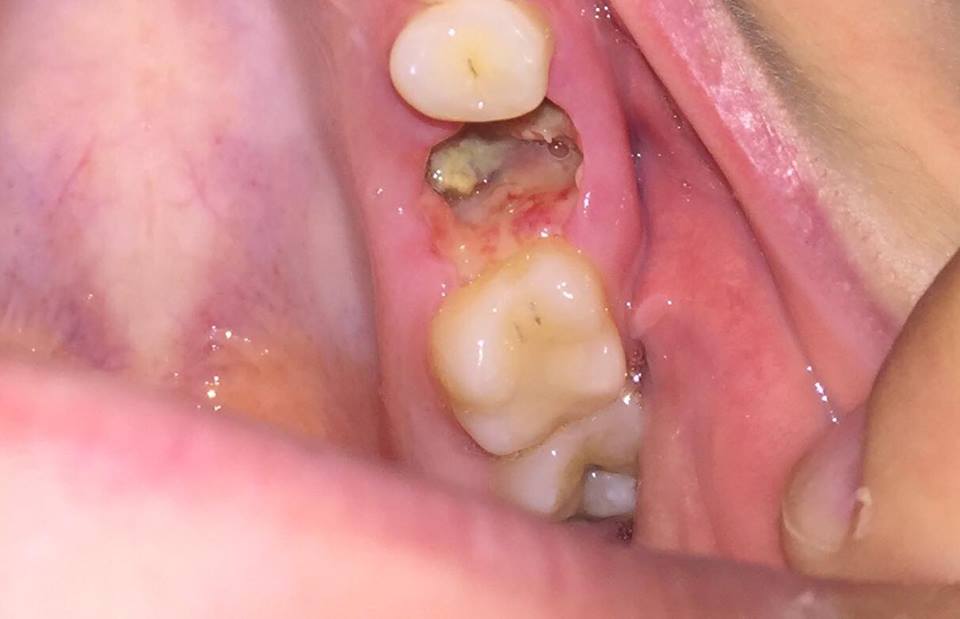

Ho estratto una radice (perche' ormai non c'era piu niente oltre che quella) superiore da 5 giorni. E' stata un *estrazione complicata* a detta del dentista e nella fattura di fatti l'ha descritta proprio cosi. Hanno impiegato circa un ora per riuscire a toglierla.

Gia da subito, quando e' terminata l'anestesia avevo un dolore lancinante il che so che e' normale dopo un estrazione ma tutto cio si prolunga ancora nel quinto giorno! Dunque tralasciando che mi ha lasciato una scheggetta di dente ( sicuramente non si sara' accorto), ho la presenza di *materiale* bianco che non e' assolutamente cibo in quanto non riesco assolutamente a mangiare e dunque non sto mangiando roba solida, a me sembra pus dato il cattivo odore pero' toccando con la lingua (so che e' cosa sbagliata) oltre a parti molli sento anche del duro e raschioso!!

Vi allego qui una foto di come si presenta il "buco" e spero possiate darmi una mano a capire!!

Buongiorno, ho letto e viste le foto: a prescindere dal frammento radicolare, sembrerebbe trattarsi di un'alveolite acuta con fase ascessuale iniziale, cioè infiammazione del sito estrattivo complicata da infezione; tenga presente però che il tessuto biancastro che si vede è probabilmente la fibrina che si forma nella fase iniziale della cicatrizzazione. Non ha impostato una terapia antibiotica? Le consiglio di tornare dal collega e farsi prescrivere un antibiotico adeguato. per il resto, ciò che fa va bene.